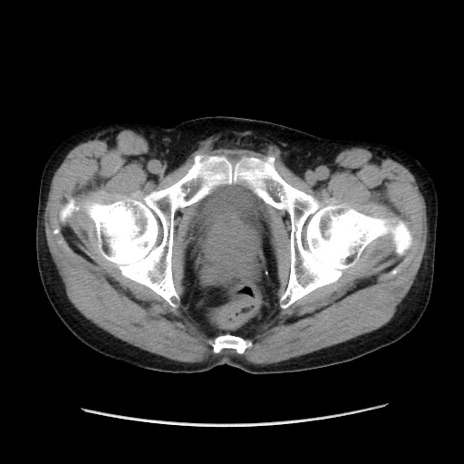

症例37(横断像)

【症例】40歳代 男性

【主訴】腹痛

【現病歴】4時間ほど前に電車に乗車中に臍部上より腹痛出現。徐々に増悪し起立困難となり、救急外来受診。生ものは数日食べていない。今朝お雑煮を食べた。

【身体所見】BT 36.8℃、BP 117/84mmHg、HR 91/min、SpO2 97%、苦悶様、腹部:臍上部広範囲圧痛あり、反跳痛±

【データ】WBC 8100、CRP 0.03